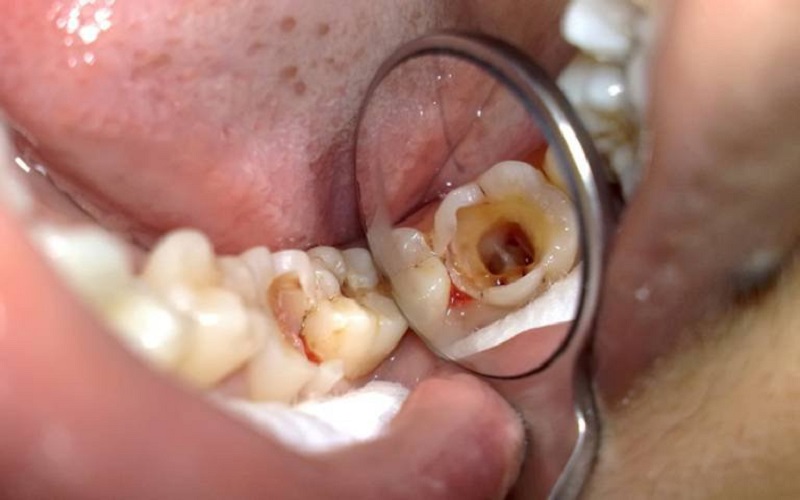

Hình ảnh răng hàm dưới bị viêm tủy

Hình ảnh viêm tủy răng không phục hồi